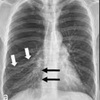

73

Dx

EPOC

74

75

Neumotorax

76

77